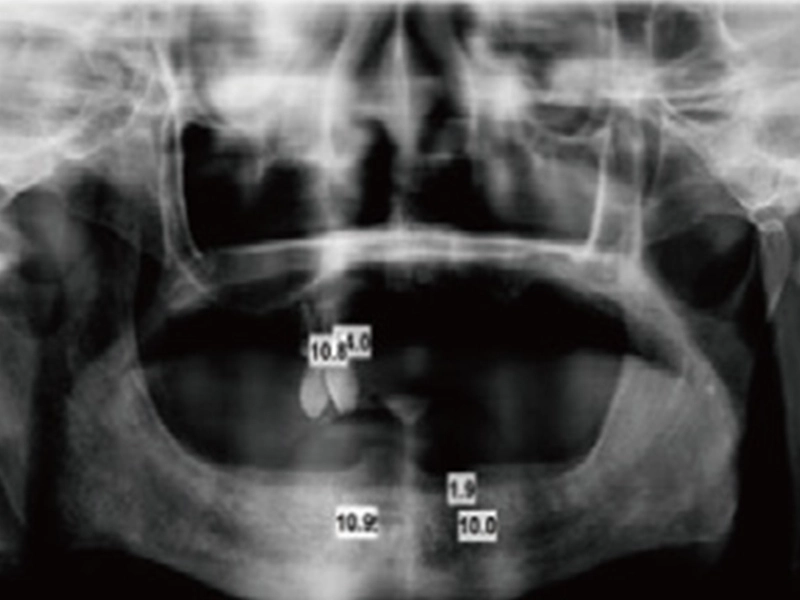

1. Take X-ray

ใช้ X-ray และ decidethe ตำแหน่งตำแหน่งสำหรับรากฟันเทียม